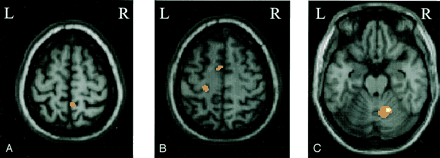

Compared with healthy volunteers, patients with no disease evolution had more significant activations of the contralateral primary somatomotor cortex (SMC) (SPM space coordinates: −22, −26, 62), contralateral supplementary motor area (SMA) (SPM space coordinates: −8, −2, 58) and ipsilateral parietal portion of the paracentral lobule (SPM space coordinates: 10, −46, 66).

Patients with Disease Evolution versus Healthy Volunteers

Compared with healthy volunteers, patients who developed MS had more significant activations of the superior frontal sulcus (SFS), bilaterally (SPM space coordinates: 26, −2, 54 and −20, −6, 46), the ipsilateral infraparietal sulcus (IPS) (SPM space coordinates: 32, −44, 68), the ipsilateral middle frontal gyrus (MFG) (SPM space coordinates: 38, −4, 54), the ipsilateral superior temporal gyrus (STG) (SPM space coordinates: 48, 12, −14), the contralateral fusiform gyrus (SPM space coordinates: −22, −52, −4), and the cuneus, bilaterally (SPM space coordinates: 22, −56, 14 and −18, −56, 4).